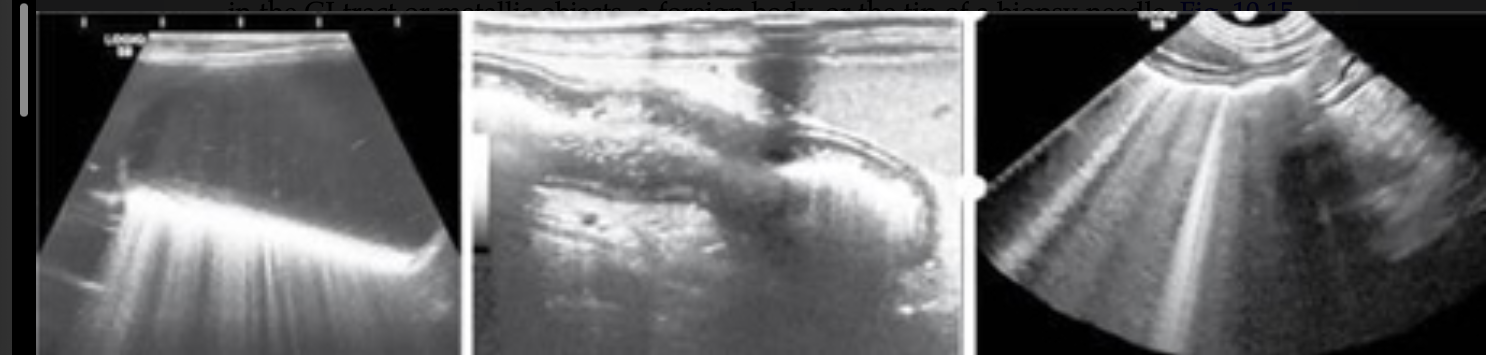

Acoustic Shadowing

occurs at interfaces that reflect and/or absorb a significant portion of the U/S beam

common with mineral interfaces (bones, calculi, foreign bodies)

Mirror Image

caused by highly reflective curved surfaces

produces duplicate of structure deep to reflective surface

most common - liver will appear in thorax due to diaphragm